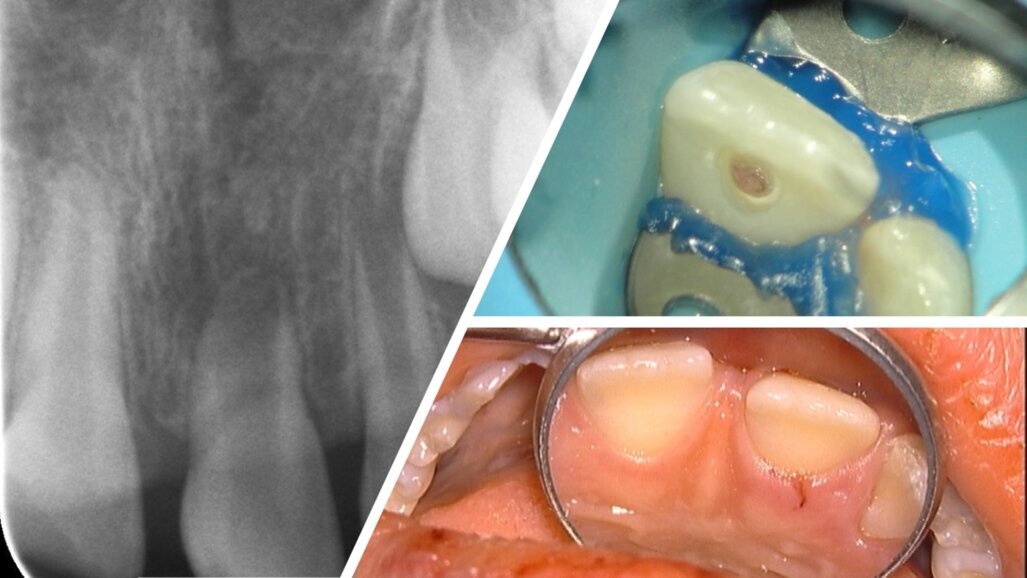

GENT – Bijna een op vijf kinderen wereldwijd heeft voor het twaalfde jaar tandschade door een ongeval. Meestal betreft het de (onvolgroeide) tanden in het bovenfront. Dit leidt niet zelden tot een ontsteking of het afsterven van de tandzenuw, waardoor de wortelontwikkeling van de getroffen tanden stopt.

De behandeling van deze tanden is technisch complex wegens de onderontwikkelde wortels. Bij verlies van de tanden zijn de esthetische, functionele, emotionele en psychische gevolgen voor de jonge patiënten niet te onderschatten.

Gebaseerd op de weefseltechnologie is de laatste twintig jaar binnen de endodontologie de revitalisatiebehandeling ontstaan. Die technologie is te vergelijken met een reanimatiepoging van een stervende tandzenuw. Het multicentrische, Europese onderzoek* naar de revitalisatiebehandeling focust zich op de klinische haalbaarheid van de tandzenuwrevitalisatie, en daarmee op het behoud van een mooie glimlach voor de jonge patiënten. De Universiteit van Gent is voor dit onderzoek via tandartsen op zoek naar geschikte patiënten en doet de volgende oproep: